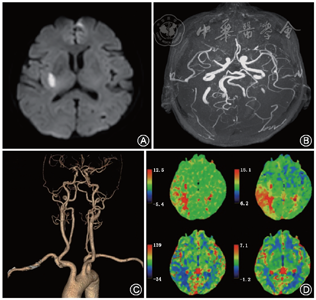

患者女性,61岁,主因“左侧肢体无力伴言语不清2 h”于2019年12月25日就诊于北京天坛医院神经内科急诊。患者平素体健,否认高血压、冠心病、糖尿病、心房颤动、心脏瓣膜病等病史,就诊时血压165/110 mmHg(1 mmHg=0.133 kPa)。患者初诊时NIHSS评分为10分,完善头颅CT平扫未见出血,于发病后3.5 h接受了重组组织纤溶酶原激活剂静脉溶栓,溶栓后2 h NIHSS评分6分。患者急诊心电图未见明显异常,住院期间完善入院常规实验室检查,低密度脂蛋白胆固醇(low-density lipoprotein cholesterol,LDL-C)3.21 mmol/L,总胆固醇6.16 mmol/L,空腹血糖5.94 mmol/L,糖化血红蛋白5.6%。患者在院期间完善头颅MRI结构影像学检查提示右侧脑室体部旁、放射冠及基底节区超急性期梗死灶(图1A);完善头颅MRA和CTA检查进行血管评价提示右侧大脑中动脉水平段存在重度狭窄(图1B、C);脑CT灌注成像(computed tomography perfusion)检查进行血流动力学评价提示右颞顶片状区域低灌注改变(图1D)。患者超声心动图及动态心电图未见明显异常。对于该患者,应如何制定二级预防策略,以降低卒中复发风险?